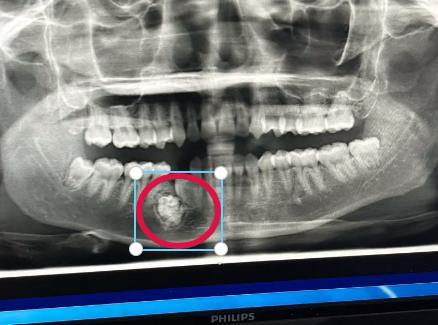

起因是这位美女自幼就缺了一颗牙,一直都没有长出来。等到成年后想要解决这个缺牙问题的时候发现缺牙处竟长出来“牙瘤”。

牙瘤是牙源性肿瘤。生长在颌骨内,主要是因牙胚组织发育异常形成的,形状不规则,数量有多有少。

经过手术,医生从美女的缺牙处取出57颗发育异常的牙齿。